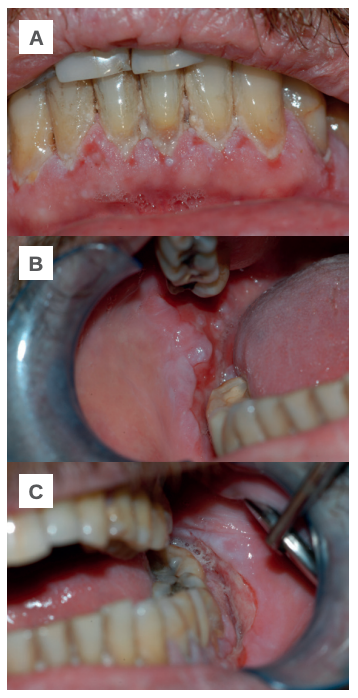

Transcurridos dos meses su dermatólogo sustituye la prednisona por 25 mg de azatioprina cada 24 horas, pero tras tres semanas es necesario interrumpir el tratamiento por fuertes molestias gastrointestinales y una ligera recidiva de las lesiones en la mucosa yugal. Con el fin de volver a estabilizar al paciente, se le prescriben bajas dosis de prednisona (10 mg cada 24 horas) con resultados positivos y una considerable remisión de las lesiones. El paciente se mantiene asintomático y sin recidiva de nuevas lesiones (Figuras 2 A- B y C).